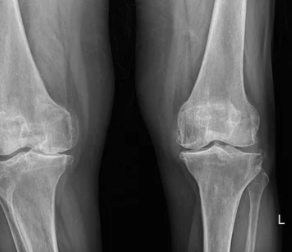

퇴행성 관절염 증상, 초기부터 말기까지 단계별 특징 정리

**퇴행성 관절염(Osteoarthritis)**은 나이가 들면서 관절의 연골이 닳아 없어지고, 관절을 이루는 뼈와 인대에 변화가 생겨 통증과 운동 제한이 나타나는 질환입니다. 흔히 ‘나이 들어 생기는 관절병’이라고도 불리며, 무릎, 손가락, 고관절, 척추 등 하중을 받는 관절에 주로 발생합니다. 이번 글에서는 퇴행성 관절염의 대표적인 증상, 초기·중기·말기별 변화, 감별 질환, 진단 및 관리법까지 자세히 정리합니다.

| X-ray(방사선 촬영) | 관절 간격 감소, 뼈 돌출(골극), 변형 여부 확인 |